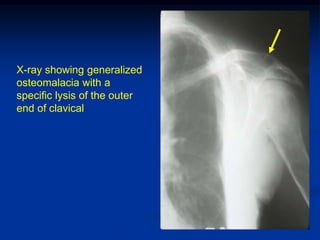

X-ray showing generalized

osteomalacia with a

specific lysis of the outer

end of clavical

X-ray showing generalized osteomalaciawith a specific lysis of the outer end of clavical